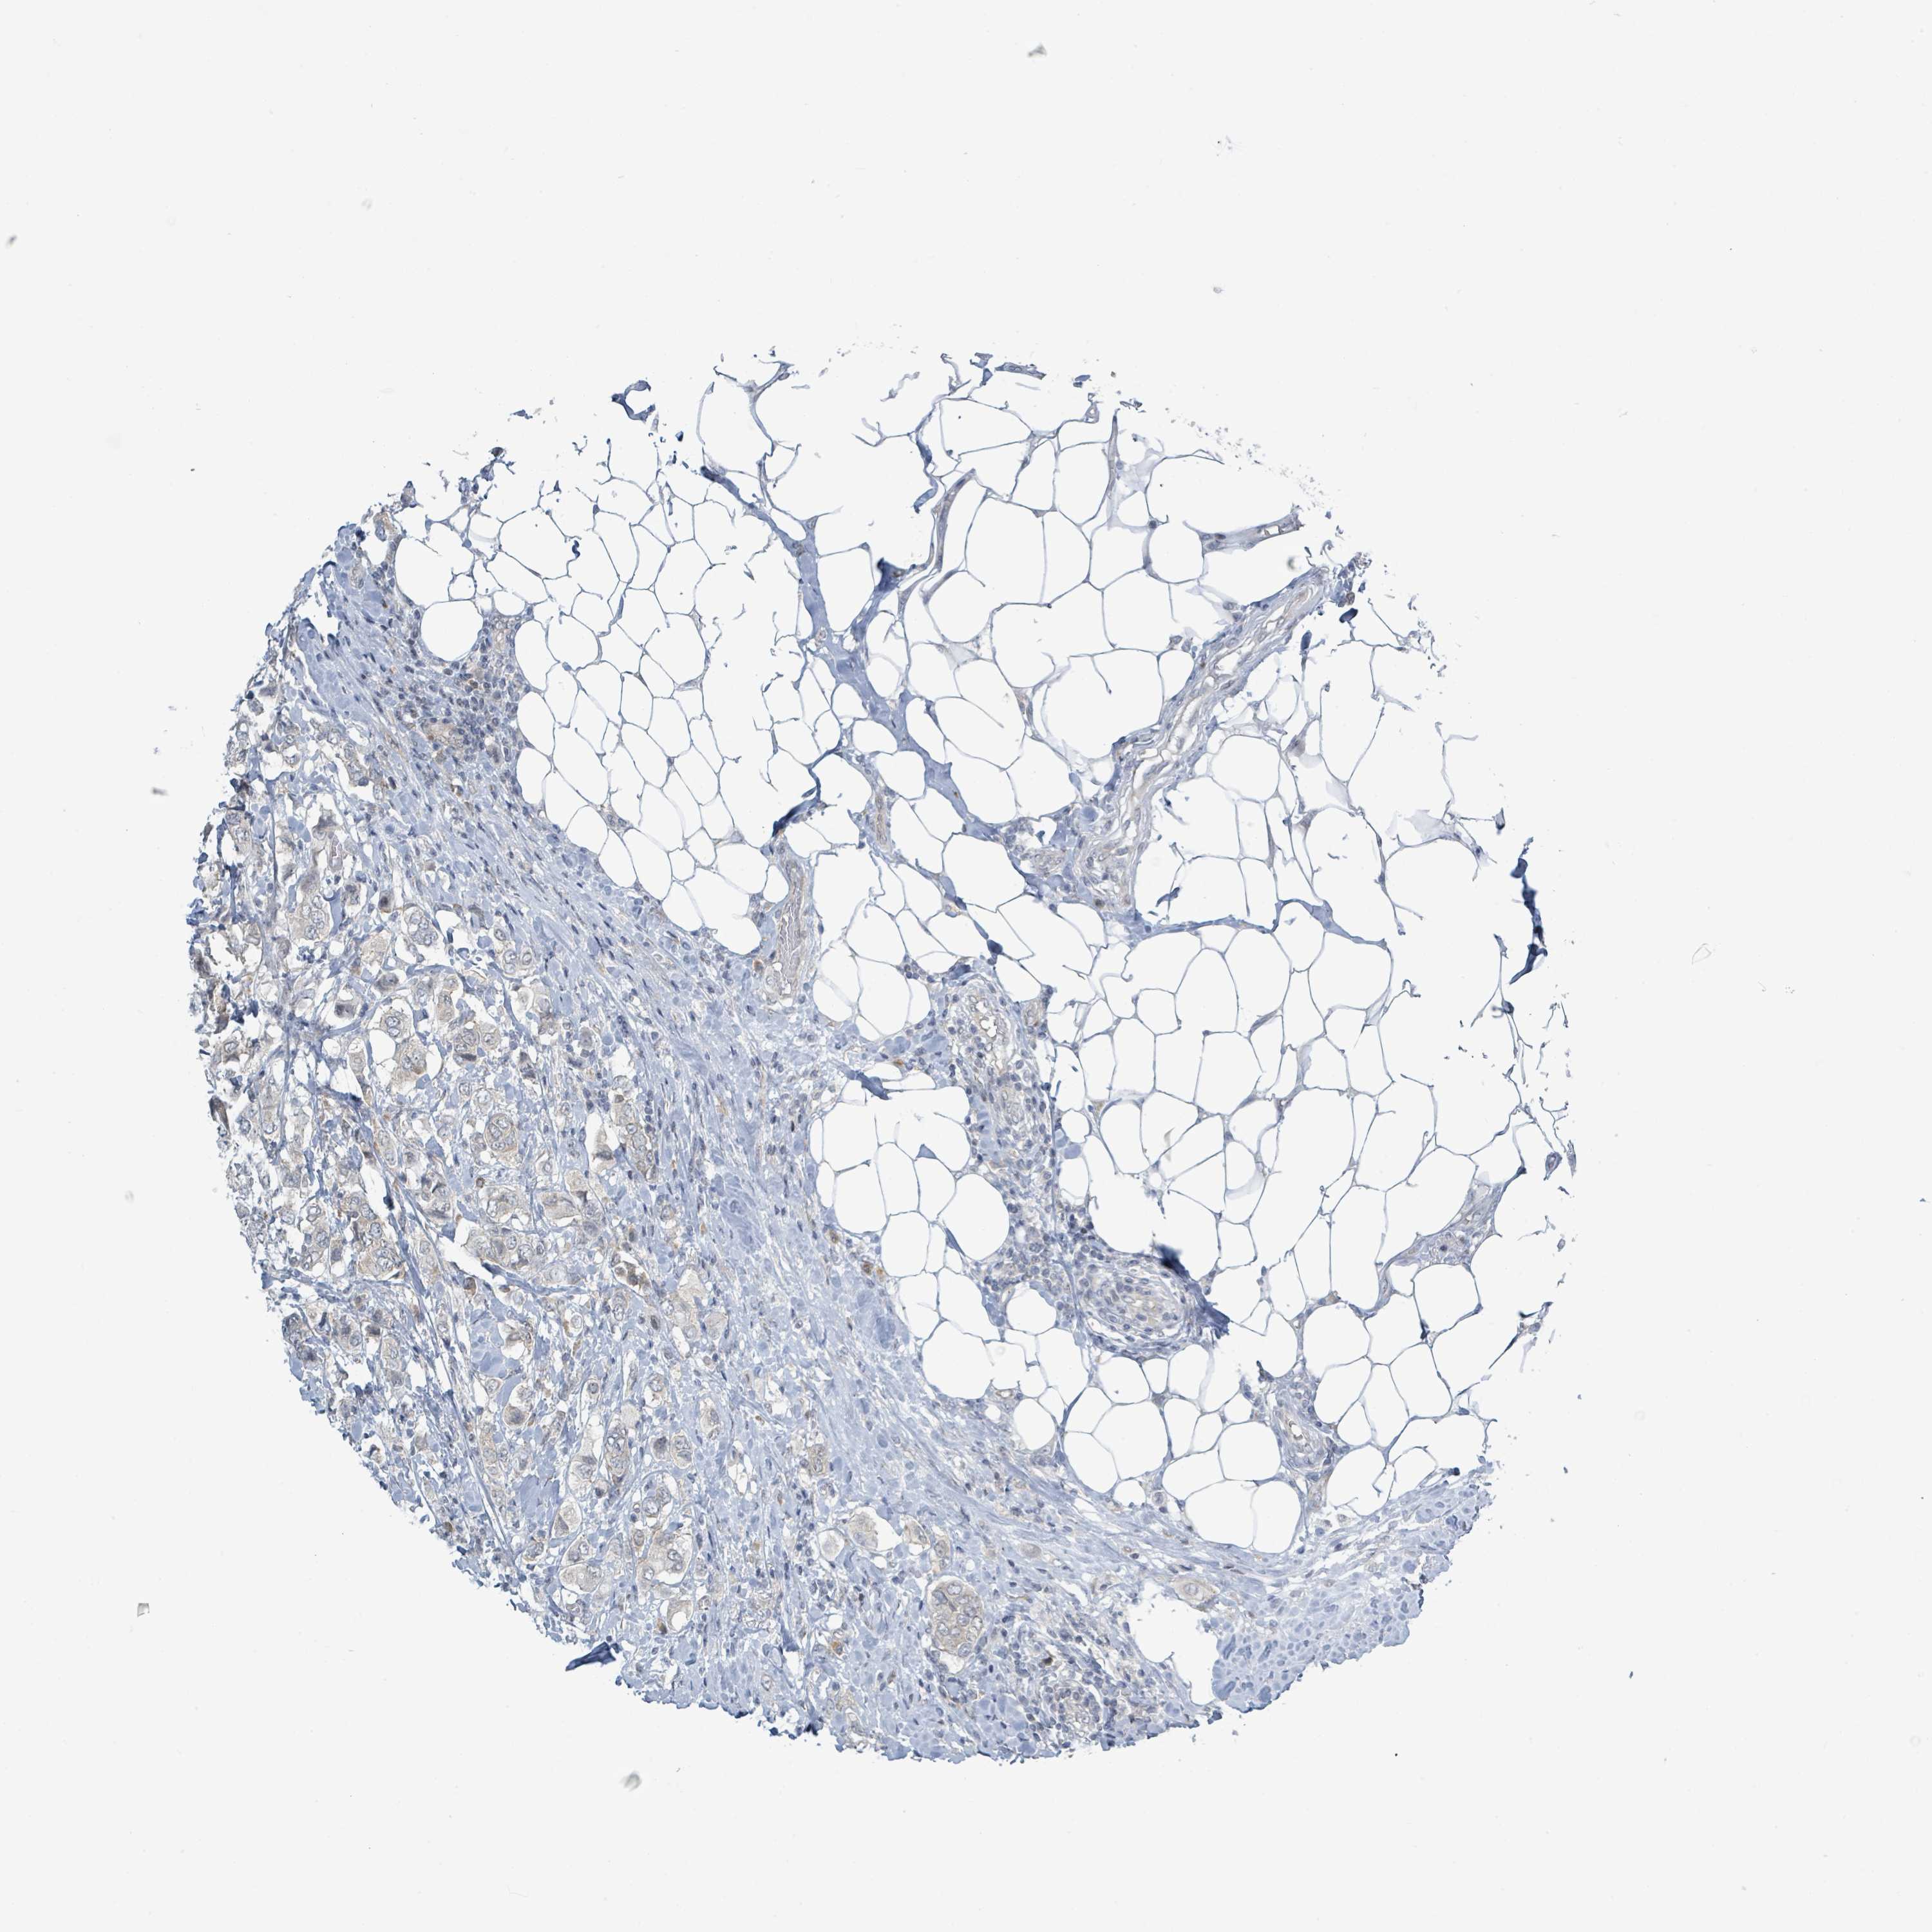

CANCER BREAST CANCER Show tissue menu

BRCA TCGA BRCA VALIDATION PROTEIN EXPRESSION

Breast cancer

Human cancer